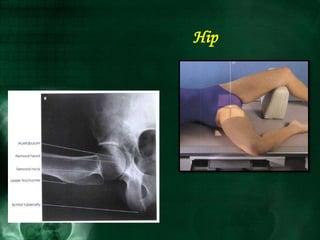

Hip

AP PROJECTION

ORIGINAL CLEAVES METHOD

NOTE: This examination is contraindicated for patients with

suspected fracture or pathologic.

Image receptor : 24 x 30 cm lengthwise

Position of patient : Place the patient in the supine

position.

Position of part :

• Adjust the patient's pelvis so it is not rotated. This is

accomplished by placing the ASISs equidistant from the

table.

• Medially rotate the lower limb and foot approximately

15 to 20 degrees to place the femoral neck parallel with

the plane of the IR, unless this maneuver is

contraindicated or other instructions are given.

Respiration: Suspend.

Central ray :

Perpendicular to the femoral neck.

• Place the central ray approximately 2 ½ inches (6.4 cm)

distal on a line drawn perpendicular to the midpoint of a

line between the ASIS an the pubic symphysis.